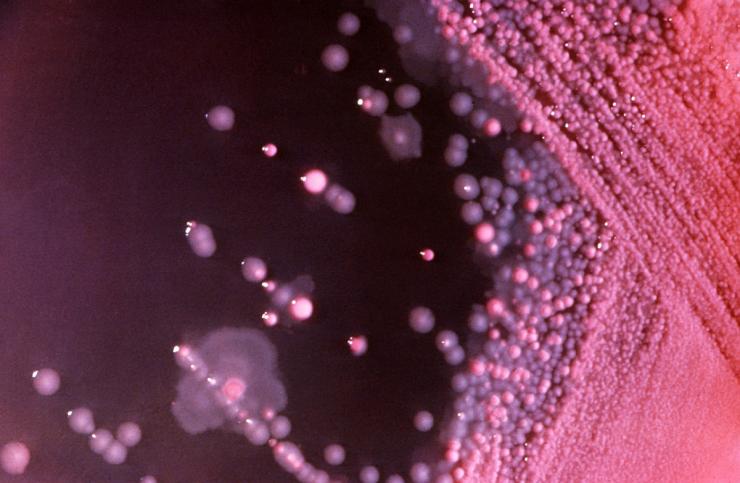

The laboratory of Dr. Robert Britton is interested in understanding how the intestinal microbiota provides a barrier to incoming pathogens and how perturbations of the microbiota result in an established infection. Most of the effort has been focused on the pathogen Clostridium difficile.

C. difficile is a gram-positive, spore-forming bacterium that is considered to be one of the three highest risk drug-resistant infections in the United States. It is an opportunistic infection that infects the colon of patients following antibiotic treatment. The microbiota that inhabit the gut normally prevent C. difficile colonization and suppress C. difficile-associated disease, but treatment with antibiotics results in changes to the composition of microbiota that allow C. difficile to grow and cause disease.

C. difficile produces toxins that damage intestinal cells and cause inflammation, producing diarrhea, and can be fatal. Of nearly 500,000 infections each year, approximately 29,000 result in death. It is the most common cause of hospital-acquired infections in developed countries. The infection is very difficult to treat, with many patients suffering from recurrent infections.

Dr. Britton, along with Dr. James Collins and other members of his research group, have developed mini-bioreactors and mice colonized with a human intestinal microbiota to determine which members of the microbial community are responsible for inhibiting C. difficile invasion. Their goal is to develop a probiotic cocktail, derived from the human intestinal microbiota, that will suppress C. difficile invasion.